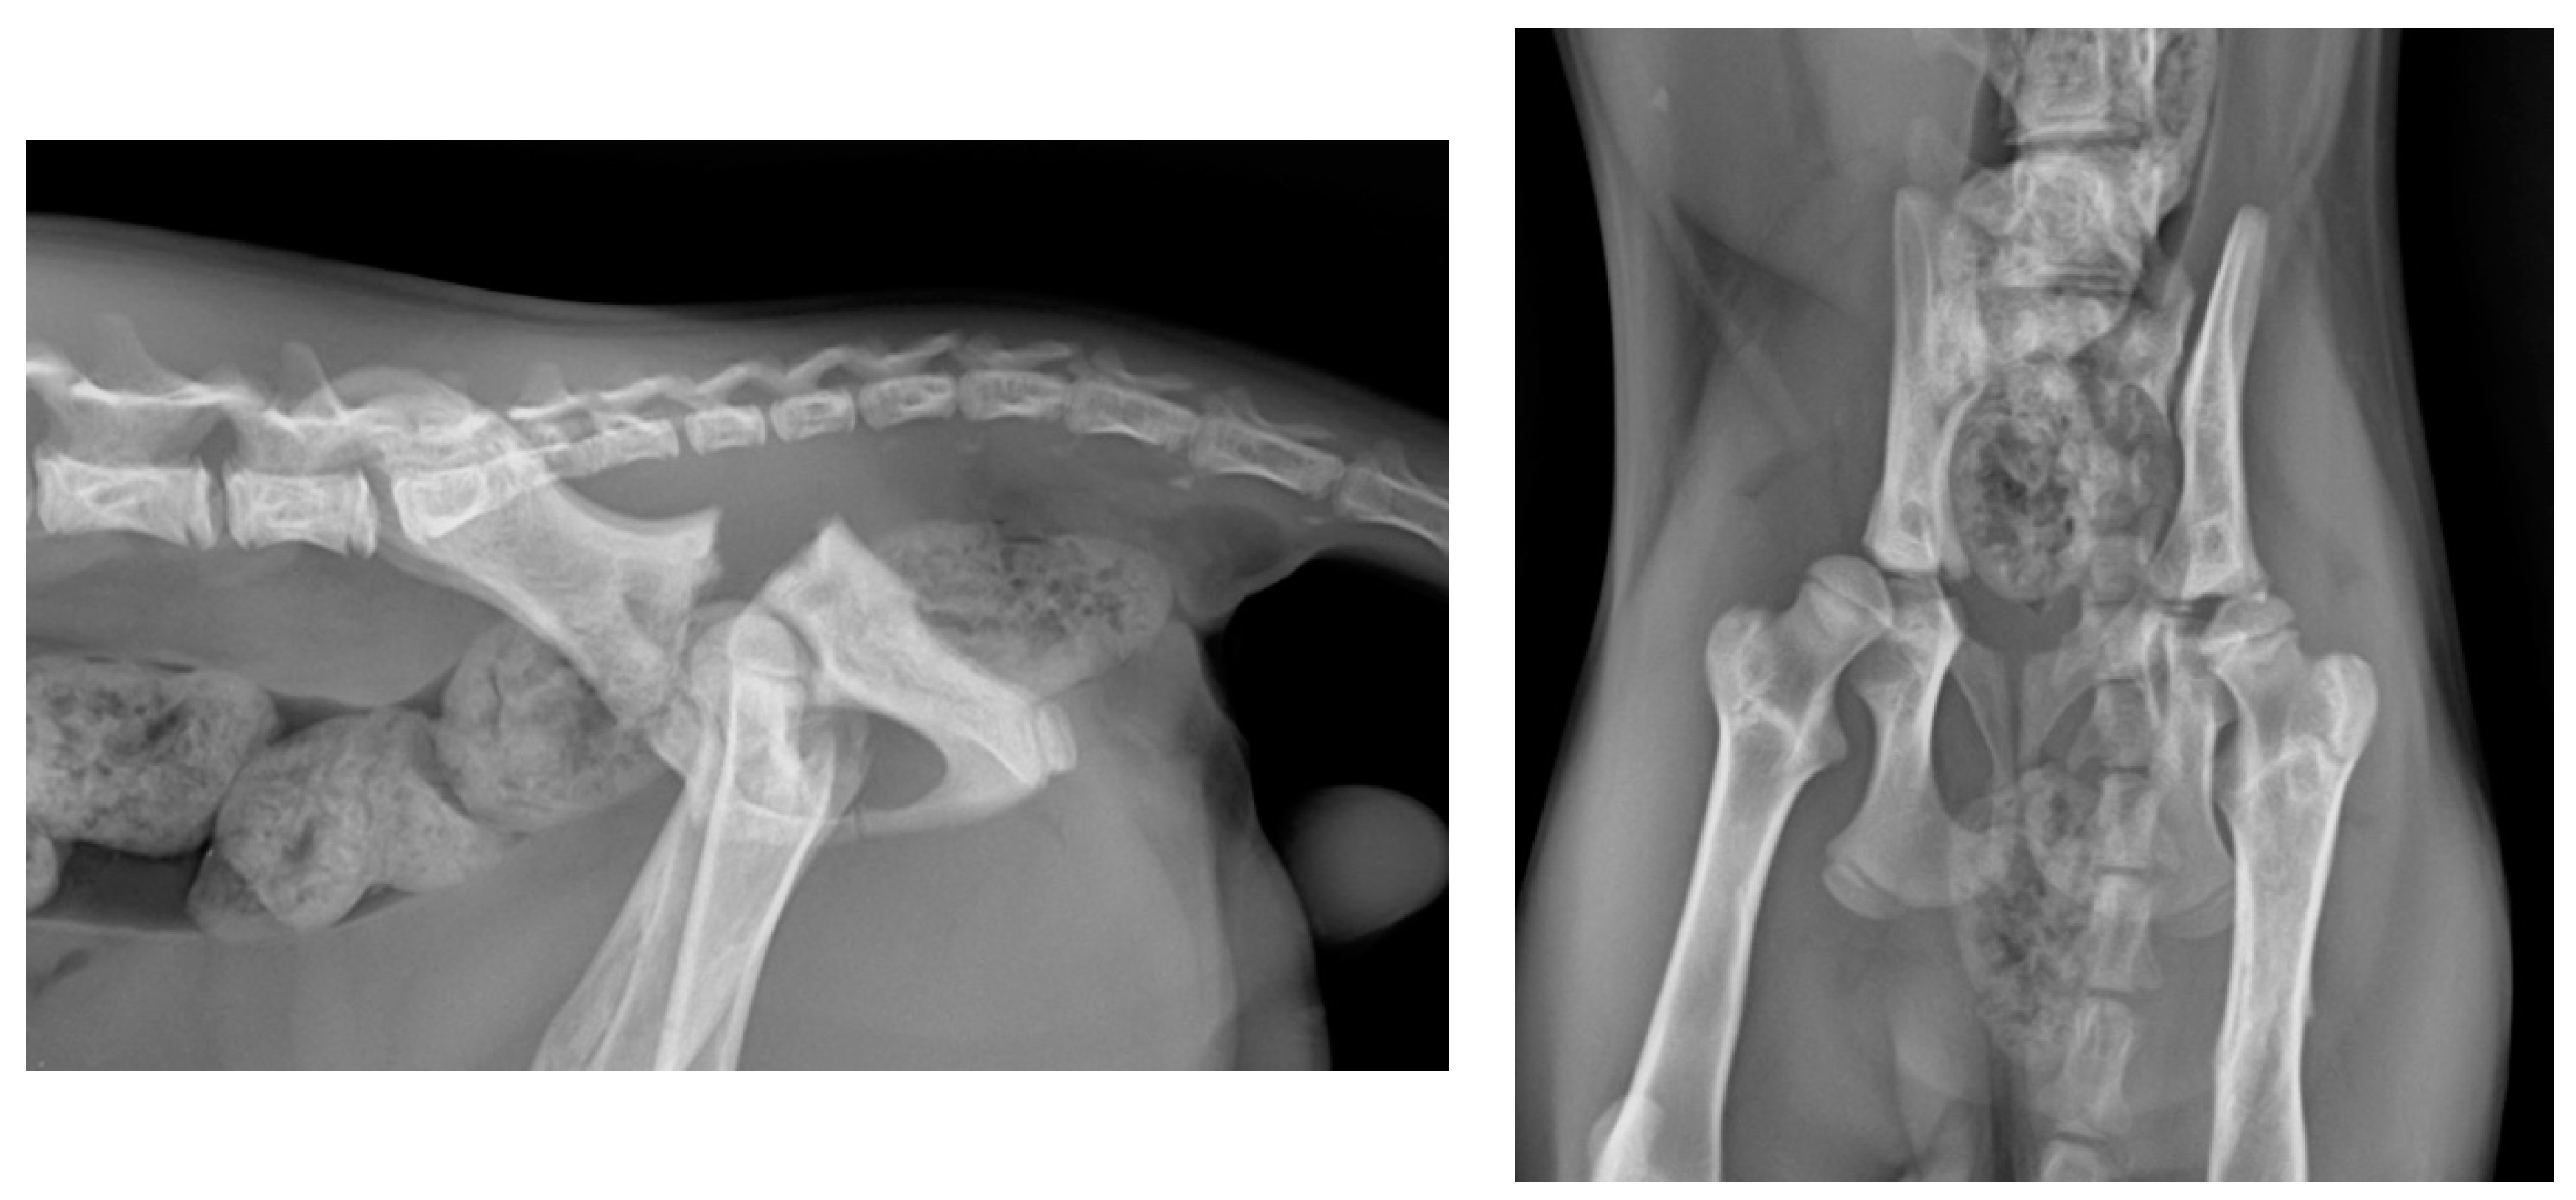

2.1. Preoperative Management

2.2. Surgical Technique